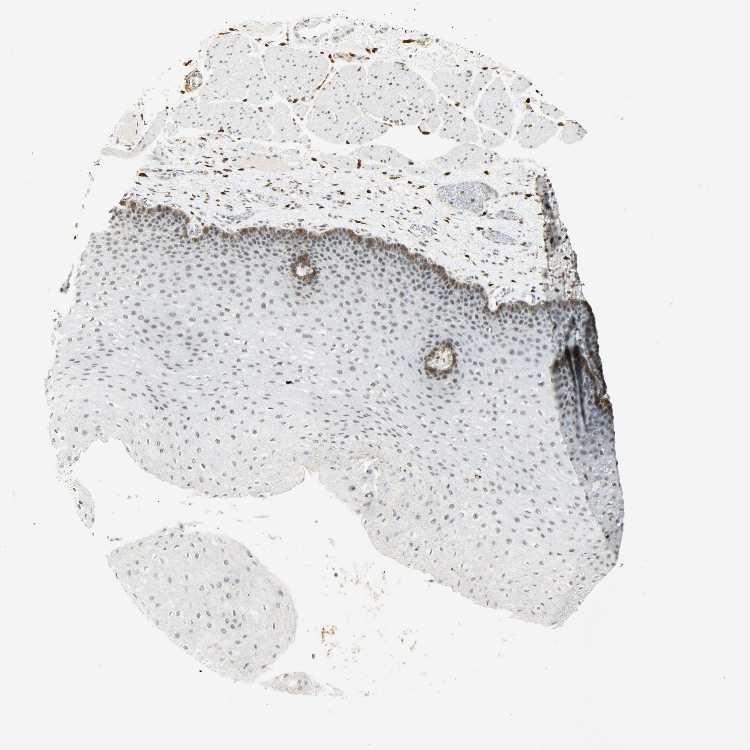

ESOPHAGUS - Antibody stainingi

Antibody staining in the annotated cell types in the current human tissue is reported as not detected, low, medium, or high, based on conventional immunohistochemistry profiling in selected tissues. This score is based on the combination of the staining intensity and fraction of stained cells.

Each image is clickable and will lead to virtual microscopy that enables deeper exploration of all samples and also displays staining intensity scores, fraction scores and subcellular localization as well as patient and tissue information for each sample.

Antibody HPA004765Antibody CAB000143Antibody CAB001995

Squamous epithelial cells MediumMediumLow